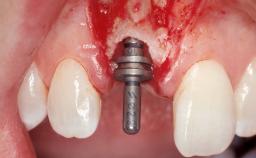

Late Flapless Placement of an Implant in a Maxillary Left Central Incisor Site

A 39-year-old male patient presented with a chief complaint of discomfort and gingival discoloration around his maxillary left central incisor. He was in good general health and was a non-smoker. His past dental history was significant because of the traumatic fracture of tooth 21 in a sporting accident at age 13. Initial dental treatment included endodontic therapy and a full-coverage restoration. The patient became symptomatic 5 years later, when structural failure of the tooth resulted in the dislodgment of the crown. Endodontic retreatment, apical surgery, and post-and-core restoration were performed.

Type of Implants One-Piece

Attachment One-Piece

Bone Augmentation Horizontal|Staged

Augmentation Materials Xenogenous|Membrane

Soft Tissue Grafting Simultaneous

Placement Protocol Early or late implant placement